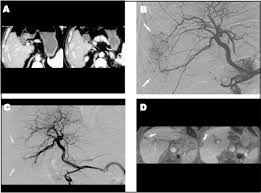

Resultado de imagen para protocolo de quimioembolización